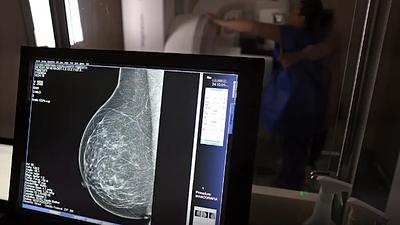

Mais mulheres chegam ao SUS no Rio para o exame de mamografia

A rede municipal do Rio tem oferta plena de mamografia e, em 2024, 153 mil cariocas realizaram o exame, que é essencial para o rastreio e diagnóstico da doença.

Cerca de 77 mil mulheres aguardam mamografia pelo SUS, diz relatório

Segundo a instituição, em alguns locais do país, o tempo de espera por uma mamografia na rede pública pode chegar a 80 dias. O exame, quando realizado em tempo hábil, permite a detecção precoce de alterações mamárias.